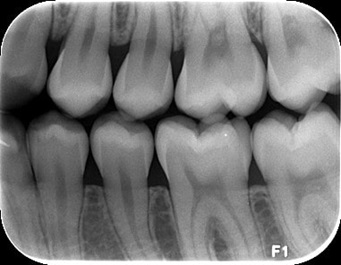

Radiografia Interproximal